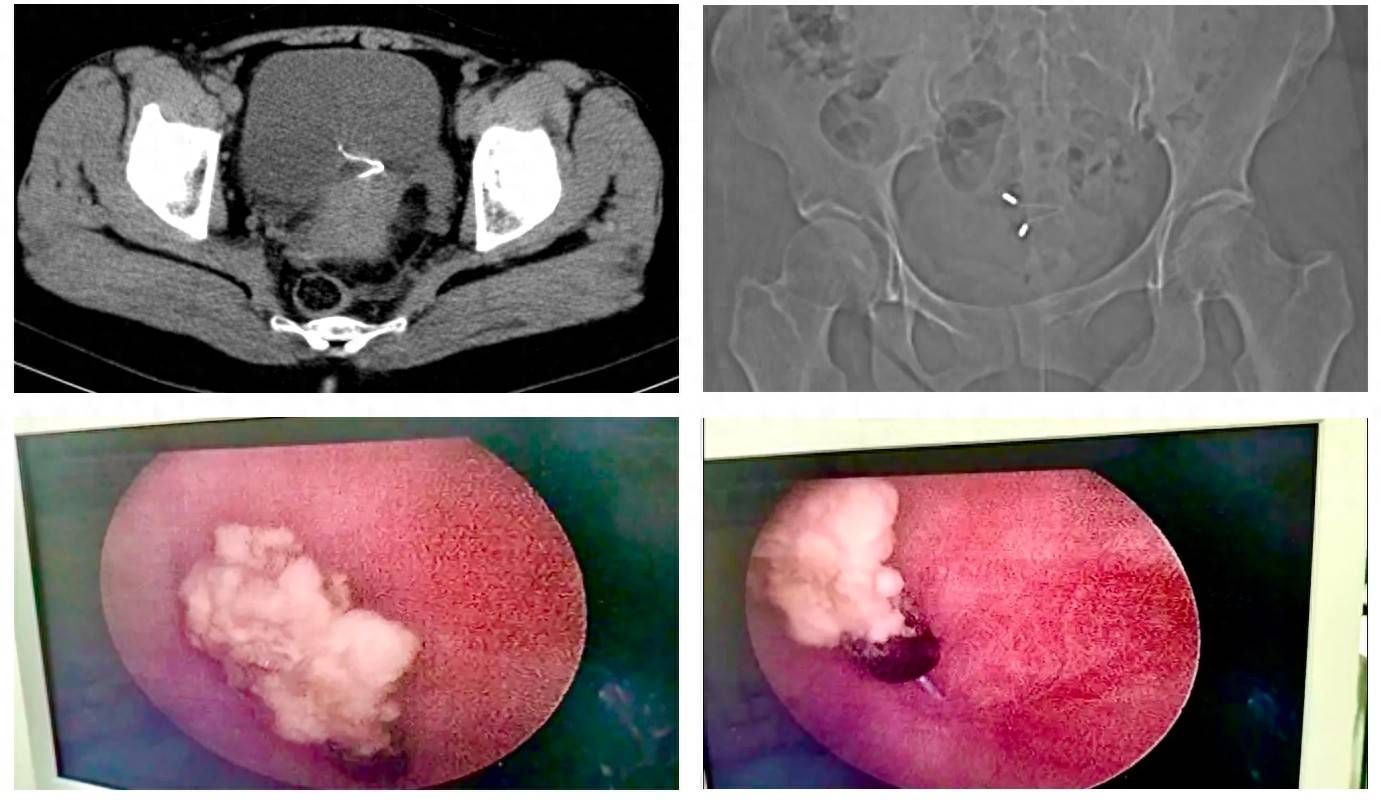

术前检查提示,节育器于膀胱内再次形成结石,未损伤输尿管开口

入院后,妇产科超声检查提示宫腔内无节育器影像。泌尿外科孔斯聪副主任医师会诊后,通过CT三维重建明确:这枚节育器已穿透膀胱全层,在膀胱浆膜外形成脓性包裹,与子宫后壁致密粘连,紧邻阴道穹隆,操作稍有不慎即可能引发泌尿生殖瘘。经多学科讨论,最终制定腹腔镜下膀胱切开取环方案。